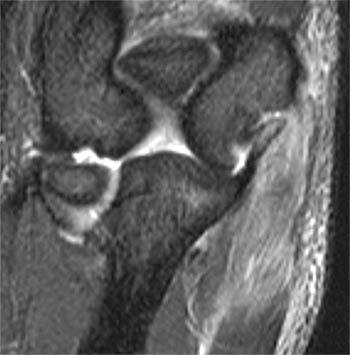

There are dozens of reasons why you might experience foot pain, ranging from simply wearing uncomfortable shoes or a stone bruise to something major like a broken bone or neuropathy. Ulnar Collateral Ligament Tears of the Elbow - Radsource

Ulnar Collateral Ligament Tears of the Elbow - Radsource from radsource.us